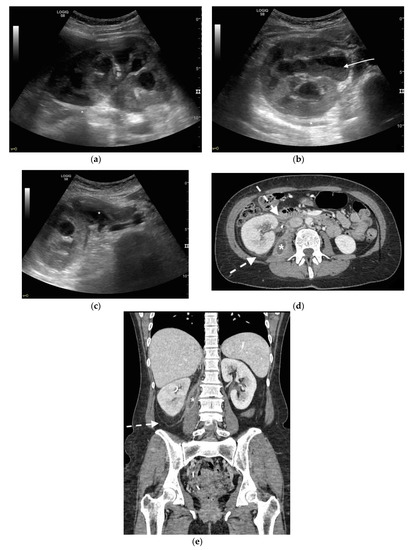

Figure 5. A 48 years old septic woman. US longitudinal (a) and axial (b,c) view of the right kidney. Enlargement of the kidney, hydronephrosis with sharply defined urine-debris level (white arrow). Thickening of perirenal fascia and markedly inhomogeneous echogenicity of perirenal fat suggesting extrarenal extension (*). The patient underwent nephrostomy in the emergency setting, and CT was performed after stent placement. Axial (d) and MPR coronal (e) CT with intravenous contrast in parenchymal phase, showing correct stent positioning (white arrow) and drainage of calyceal-pelvic system. The right kidney appeared enlarged with a delayed parenchymal phase, the calyceal-pelvic system was unstretched after nephrostomy placement. Right perirenal fascia was thickened posteriorly (dashed arrow) and extrarenal extension of the pathology was confirmed by the presence of an abscess in the right iliopsoas muscle (*).